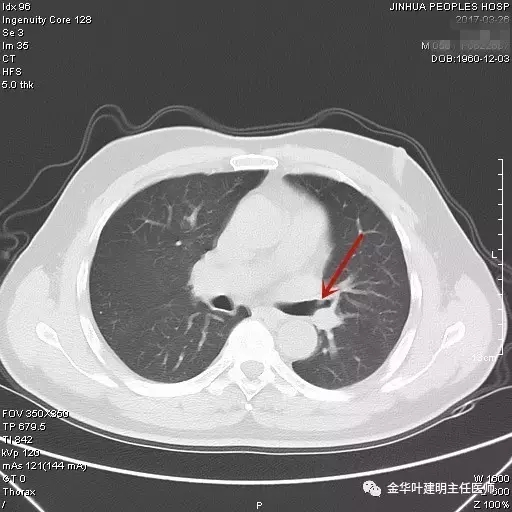

图一:红色箭头所指处示左肺上叶开口处的病灶,不仔细看根本发现不了,也极易漏掉